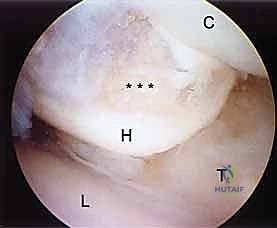

1. The Midcarpal Radial Portal (MCR)

- Location: Approximately 1 cm distal to the 3-4 portal. It is bounded radially by the ECRB tendon and ulnarly by the EDC tendons.

- Anatomy: This portal enters the midcarpal joint, providing a view of the scaphoid, lunate, capitate, and hamate articulations.

- Neurovascular Risks: Generally safe, but the superficial radial nerve branches can be in the vicinity more radially.

- Function: A primary viewing portal for midcarpal arthroscopy, allowing triangulation with the midcarpal ulnar portal for instrumentation. Essential for probing the SLIL and LTIL joint spaces for instability and assessing chondral lesions.

2. The Midcarpal Ulnar Portal (MCU)

- Location: Similarly located 1 to 2 cm distal to the 4-5 portal. It is bounded by the EDC and the EDM tendons.

- Anatomy: Enters the midcarpal joint, providing views of the lunotriquetral articulation, hamate, and capitate.

- Neurovascular Risks: The dorsal cutaneous branch of the ulnar nerve is at risk here.

- Function: Complements the midcarpal radial portal for triangulation, allowing instrumentation for débridement, loose body removal, or chondroplasty.